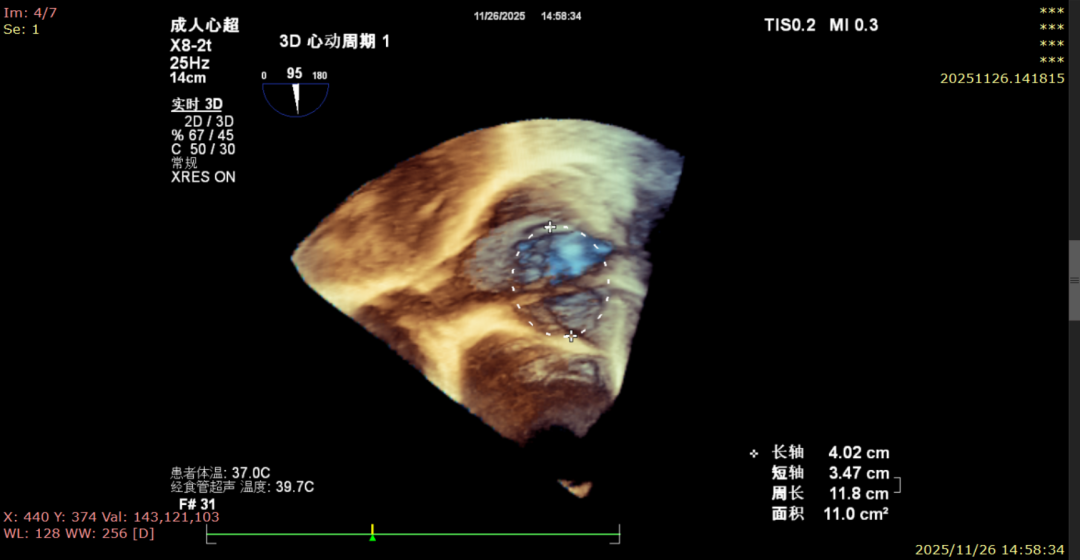

Postoperative

Mild regurgitation (1+)

Annular area: 11.0 cm² (1100 mm²)

Immediate postoperative echocardiographic evaluation showed that tricuspid regurgitation was reduced from severe (4+) to mild (1+), with a 30% reduction in annulus area. No adverse events such as atrioventricular block, valve laceration, or cardiac tamponade occurred intraoperatively or postoperatively. Concurrent right coronary angiography confirmed no compression or distortion of the coronary artery course and normal blood flow perfusion. The patient recovered smoothly after the procedure, and right heart failure symptoms were significantly improved at discharge.